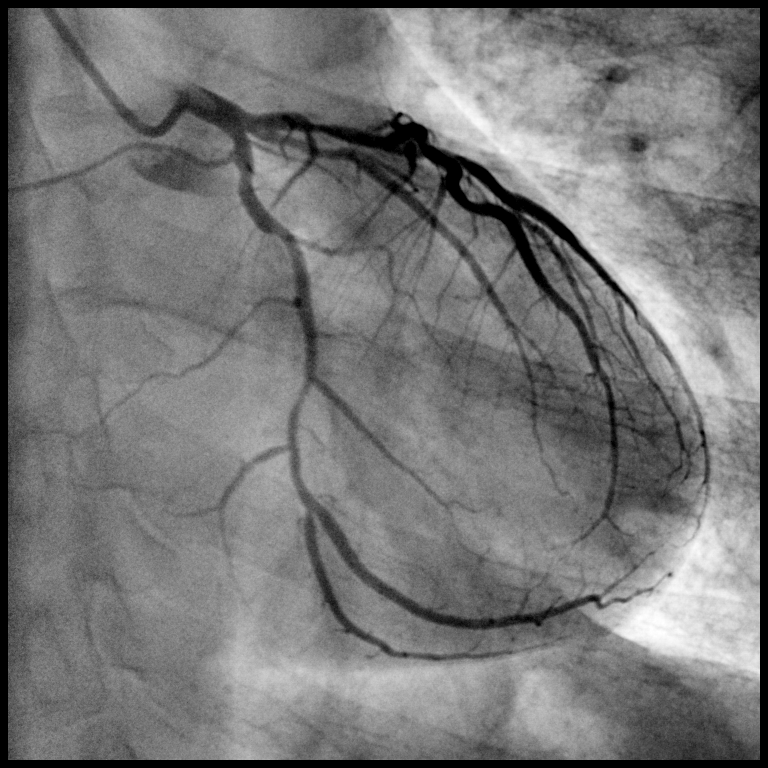

血管造影術(shù),精準(zhǔn)診斷疾病

經(jīng)外周血管穿刺引入導(dǎo)管,經(jīng)導(dǎo)管向血管內(nèi)注入對比劑使血管內(nèi)腔顯影以診斷血管疾病,是診斷血管病的“金標(biāo)準(zhǔn)”。根據(jù)導(dǎo)管進入血管的部位和深度分為3類:

1非選擇性血管造影

與心臟相連的大血管造影,如主動脈、肺動脈和腔靜脈,診斷大血管病變及顯示相關(guān)血管分支。

2選擇性血管造影

大血管的一級分支血管造影,用于整體性顯示某一臟器或某一區(qū)域供血,顯示病變、病變的病理血管、病變與正常血管的關(guān)系等。

3超選擇性血管造影

大血管的二級或二級以上分支血管造影,用于直接顯示器官內(nèi)的病變、病變的血管構(gòu)造。有心臟造影、動脈造影、靜脈造影和淋巴管造影等。